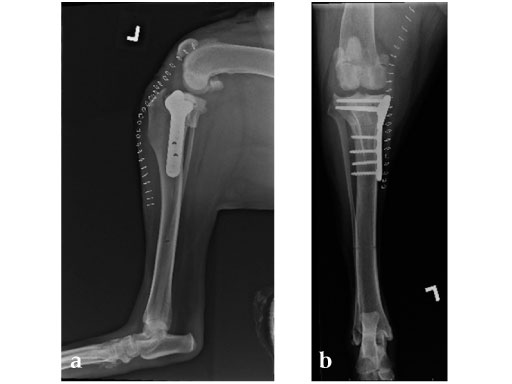

Case 2: Four-year-old English bulldog

(Case provided by Brian Beale, Houston, USA)

A four-year-old, female, spayed, 33 kg English bulldog had a CrCL tear and a medial patellar luxation. The small stature 3.5 mm TPLO plate was perfect for this dog due to the small profile of the bone and the need to use a heavier plate (3.5 vs a 2.7 mm). In the past, veterinary surgeons have been forced to either squeeze the standard TPLO 3.5 mm plate on the bone or use an undersized TPLO 2.7 mm plate. In this patient, the shorter and smaller profile head of the small stature TPLO 3.5 mm was perfect.